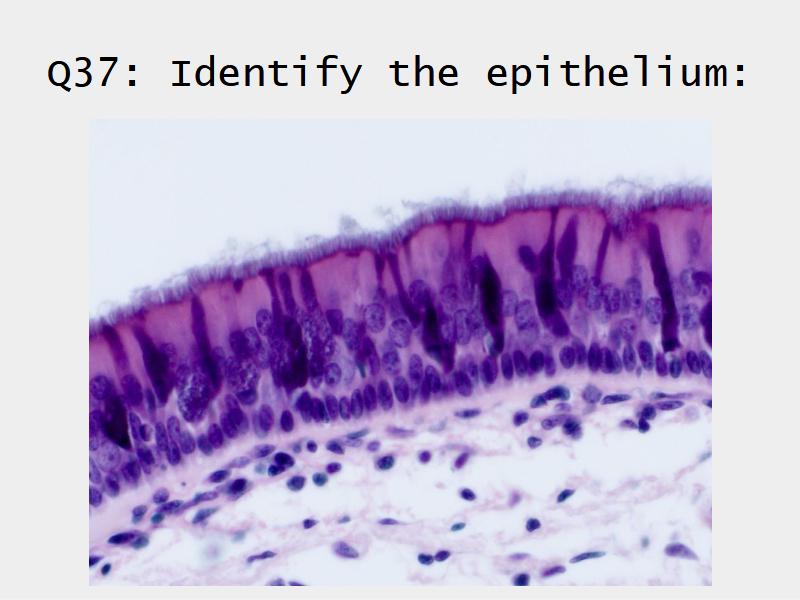

Respiratory epithelium

- Pseudostratified

- Ciliated

- Columnar

- Epithelium with

- 4 Cells

- Ciliated columnar cells

- Non-ciliated columnar cells

- Goblet cells

- Basal cells